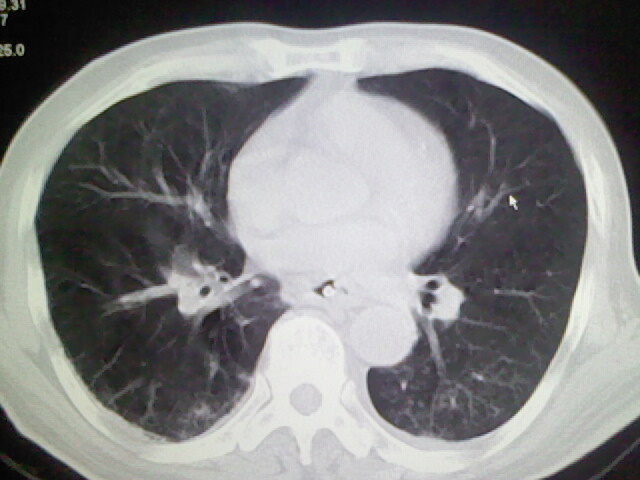

男,70岁,脑出血,长期卧床,左侧背部可触及肿块

考虑右肺及左肺下叶炎症。

右肺及左肺下叶炎症。

考虑右肺及左肺下叶慢性炎症。

肺部感染,背部筋膜增厚,考虑坠积性水肿或炎症

右侧肺部见片状密度增高影,边缘模糊。考虑炎症。另食管壁增厚。

右肺肺气肿并炎症。